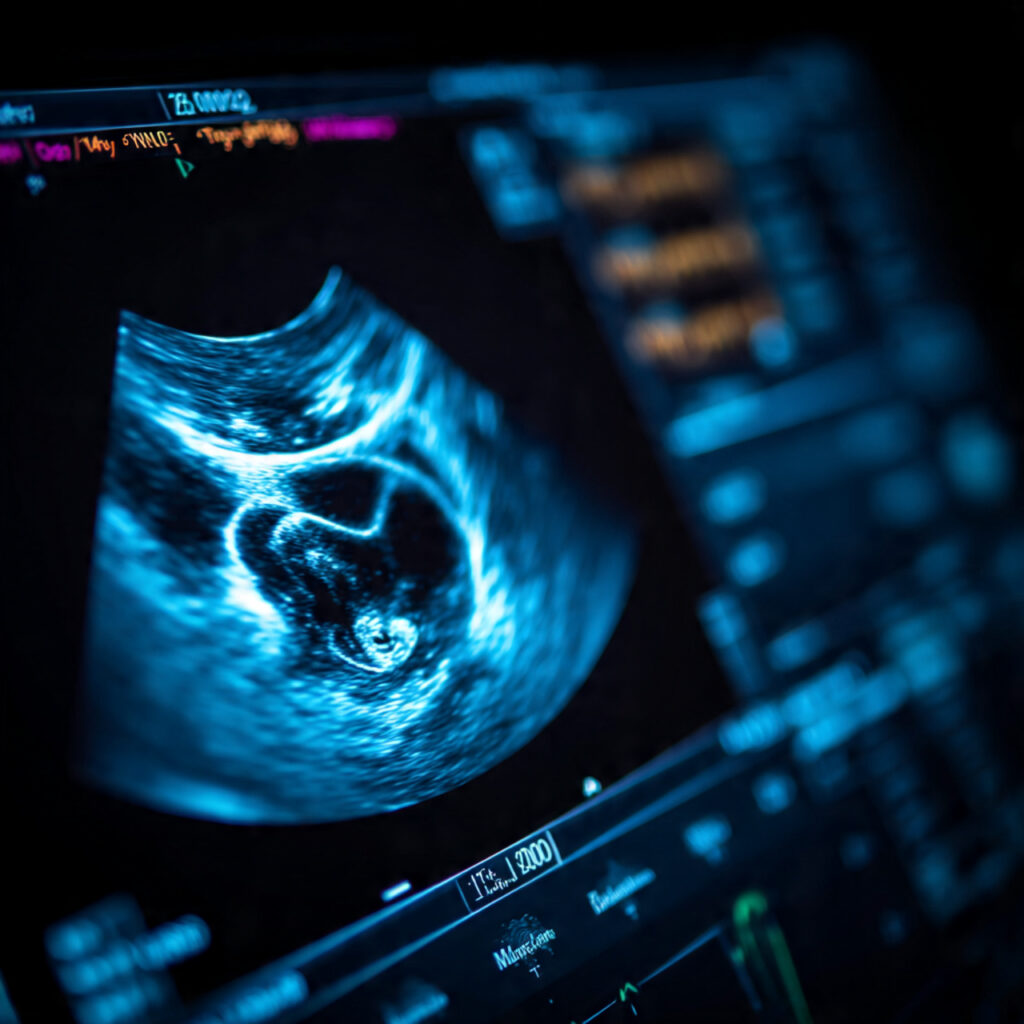

Hearing terms like “cord around the neck,” “nuchal cord,” or “cord loop” during a pregnancy scan can make many parents anxious. This is one of the most common questions expecting mothers ask when they visit Nisarga Diagnostics, Sanjaynagar, for their routine ultrasound or 3D/4D scans. The umbilical cord is the baby’s lifeline, and anything related to it naturally feels concerning. But the good news is that most umbilical cord loops are completely normal and harmless, and they do not affect the baby’s health or development. This blog explains everything clearly so parents feel confident and reassured.

Yes. A cord loop around the neck is extremely common and is seen in nearly 1 in every 3 pregnancies. During pregnancy, the baby floats freely in the amniotic fluid—just like a fish in water—while the umbilical cord also moves and floats naturally. This makes it easy for loops to form around the baby’s neck, shoulder, hand, leg, or body. In fact, when we perform pregnancy scans , especially in our , we see cord loops very frequently. In 90–95% of cases, these loops do not cause any problems at all.

At Nisarga Diagnostics, Sanjaynagar, we perform advanced scans to ensure the baby is safe. Ultrasound scans help identify loops, while Doppler studies measure blood flow in the cord. If needed, a Non-Stress Test (NST) checks the baby’s heartbeat in response to movement. These tools together provide a complete picture of fetal well-being.